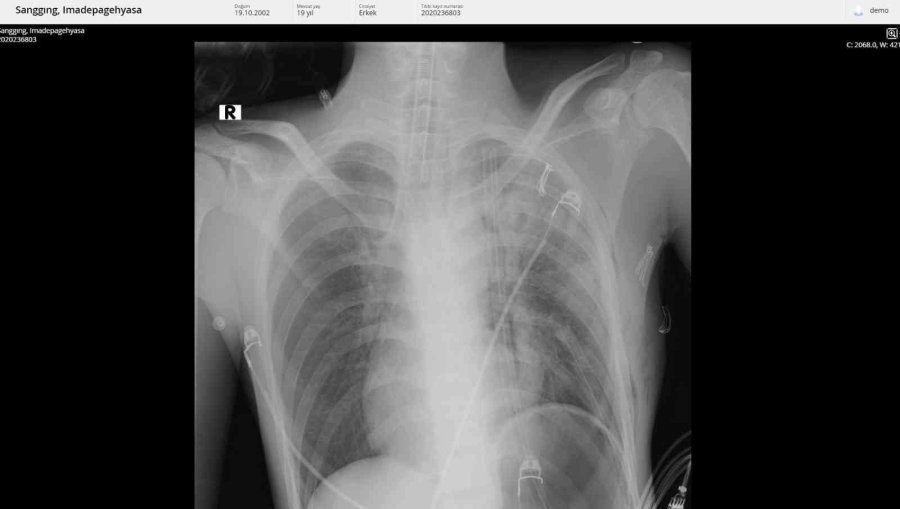

Tatil için Alanya'ya gelen 19 yaşındaki Endonozyalı I Made Pagehyasa Sanggıng, ağzından öksürükle birlikte kan gelmesi şikâyetleri ile Alanya Eğitim ve Araştırma Hastanesi Acil Servise başvurdu. Yapılan tetkik ve görüntülemeler neticesinde Sanggıng'ın sağ akciğerin tamamen fonksiyon dışı kalmasına yol açan bir kitle tespit edildi. Kitlenin ayrıca kalbe ve diğer hayati organlara da ciddi bir baskı oluşturduğu belirlendi. 19 yaşındaki hasta ALKÜ Tıp Fakültesi Göğüs Cerrahisi Anabilim Dalı Başkanı Dr. Öğretim Üyesi Oktay Aslaner tarafından acil ameliyata alındı. Başarılı geçen operasyon sonunda hasta yeniden sağlığına kavuştu. Hastanın yeniden sağlığına kavuştuğunu ifade eden Dr. Aslaner, "Acile başvuran Endonezyalı hastamızda tetkikleri sonucunda sağ göğüs kafesinin içinde dev bir kitle tespit edildi. Kalbi tamamen karşı tarafa itmiş, sol akciğerin ana atar damarını nerdeyse kapatmış şekildeydi. Ekibimle birlikte ameliyata aldık. Ameliyatta sağ göğüs kafesinden iki akciğer arasında köken alan ve sol hemotoraksı dolduran 3 kilo ağırlığında bir kitle çıkardık. Sonrasında hastanın akciğeri açıldı, kalbi rahatladı, akciğer atar damarı normal hale geldi. Kitlenin tamamen çıkarılmasıyla birlikte hasta yeniden sağlığına kavuştu. İlerleyen tıbbi cihazlar ve hastanemizdeki yoğun bakım olanakları bu tür ilerlemiş tümörlere müdahale imkânı sağlamaktadır" dedi.